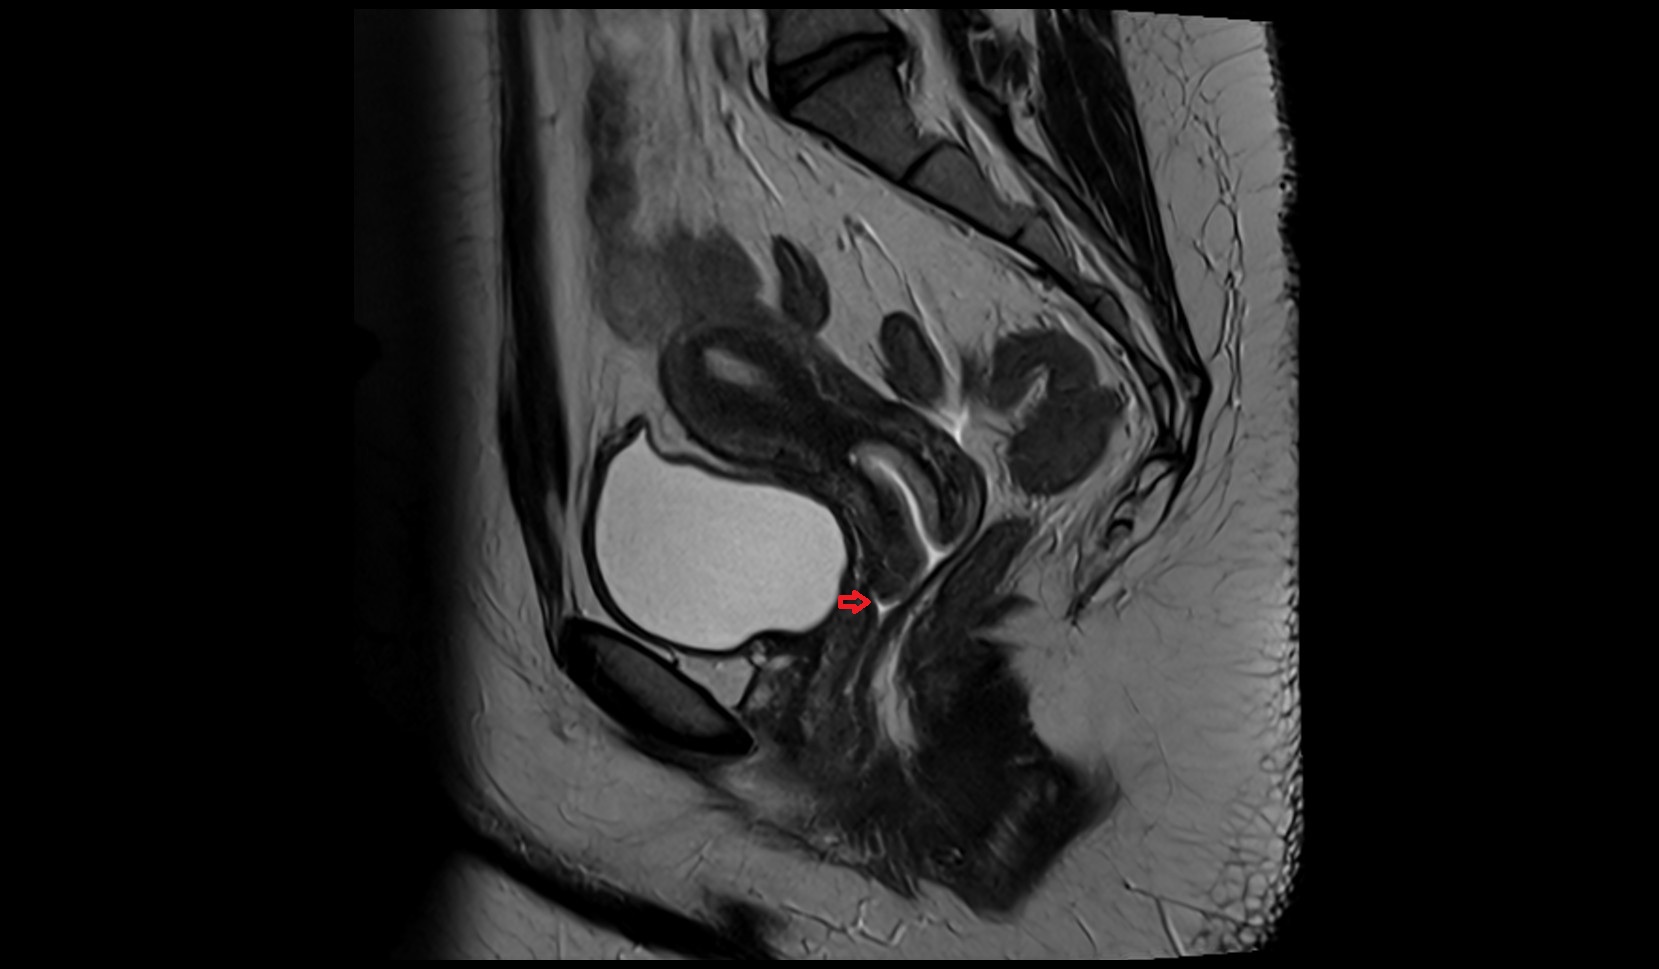

- Uterus

- Body of uterus

- Fundus of uterus

- Cervix of uterus

- Isthmus of uterus

- Vagina

- Fornix of the vagina

- Endometrium of uterus

- Myometrium of uterus

- Perimetrium of uterus

- Junctional zone of uterus

- Vesicouterine pouch

- Rectouterine pouch (pouch of Douglas)